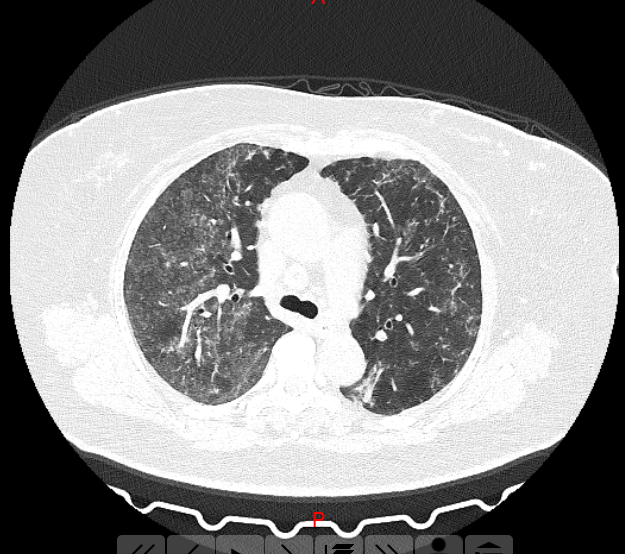

王女士肺部CT

肺部CT均呈毛玻璃影,难道是新冠病毒?

郑州市中心医院高新区医院管床医师李凤芝反复追问病史,两位均无流行病学史,隔离病区主任张小红看完患者的影像学资料及各项检查结果后说:“这两位患者考虑为过敏性肺泡炎,现在我们必须详细询问病史,了解过敏的物质。”

张小红主任:“张女士和王女士是84消毒液引起的过敏性肺泡炎!”经过3天的抗过敏治疗后复查胸部CT,影像基本恢复正常!